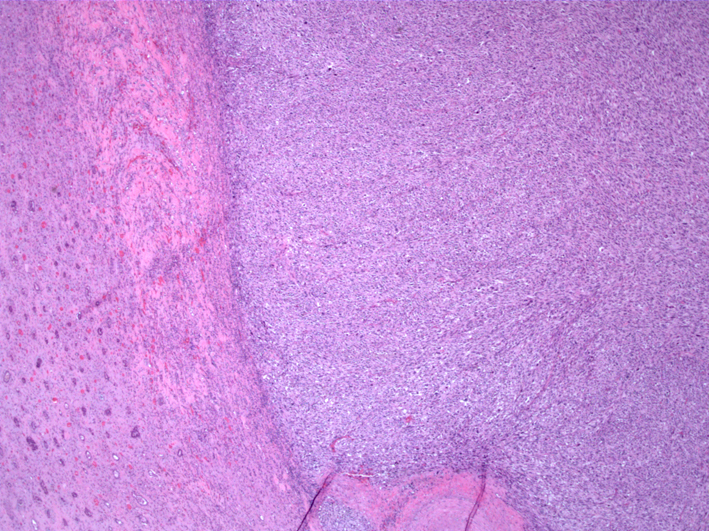

On the hemisection of the kidney by pathology, a tan mass measuring 8.0 × 7.5 × 7.5 cm was found to occupy the entire upper pole of the kidney. Adjacent ureter, renal vessels and lymph nodes were disease-free with no definitive evidence of lymphovascular invasion. Surgical margins were negative. Upon microscopic evaluation, numerous spindle tumor cells were present adjacent to uninvolved kidney parenchyma (Fig. 2). An interlacing fascicular pattern was observed in groups of spindle cells (Fig. 3). Immunohistochemical analysis revealed that the tumor was positive for smooth muscle actin, caldesmon (Fig. 4), and vimentin, but was negative for S100, BCL2, CAM5.2, CK7, CD34 and desmin.

![]() Click for large image | Figure 2. Sharply demarcated, spindle tumor cells are seen adjacent to uninvolved kidney parenchyma (HE, × 40). |